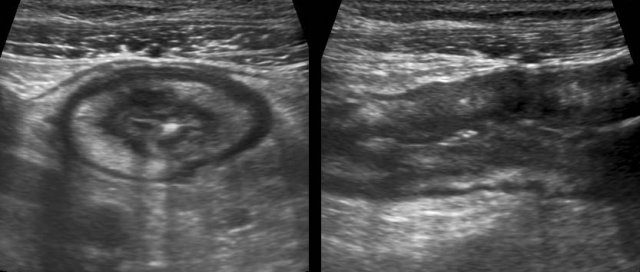

Difference between size and compressibility of normal ileum (left) and  Crohn affected ileum during intermittent graded compression.

Using graded compression, two adjacent bowel segments are compressed against the iliopsoas muscle.

The ventral segment is normal and is easily compressed, while the Crohn’s loop can hardly be compressed.

Measuring bowel wall thickness is best and most reproducibly performed during compression, as here in a normal individual (left) and in a patient with Crohn’s disease (right).

Measurements are performed from outer contour of the muscular layer to the opposite side, and then divided by 2, resulting in a wall thickness of 1.5 mm and 6.5 mm for normal resp. Crohn ileum.